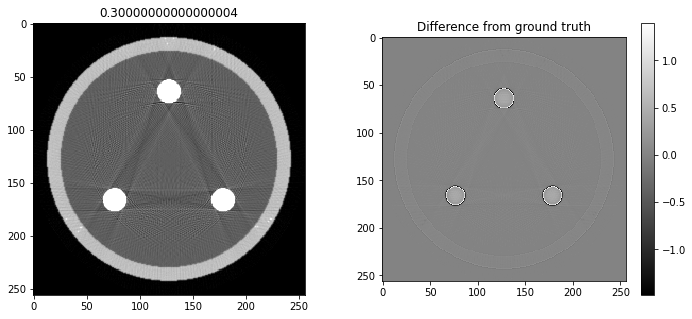

# Question 12

search = np.linspace(0,1,11)

for alpha in search:

rec = out+alpha*reproj

f,ax = plt.subplots(1,2,figsize=(12,5))

ax[0].imshow(rec,vmin=0,vmax=0.5)

ax[0].set_title(alpha)

im = ax[1].imshow(img[80]-rec)

f.colorbar(im,ax=ax[1])

ax[1].set_title('Difference from ground truth')

plt.show()